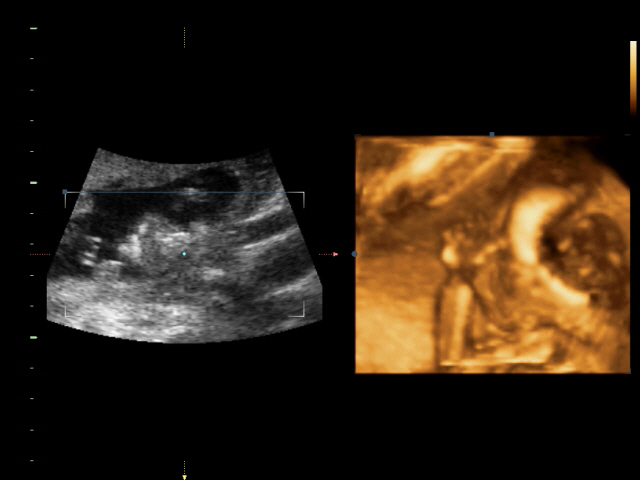

УЗИ, КТГ, доплерСходили всей семьей на 4D УЗИ! Определили нам пол окончательно и бесповоротно! Мальчик! Показали писюн! Так здорово! Я просто поверить не могу! А ведь он мне два раза снился! Настоящий реальный мужчина! Все показатели у нас в норме.